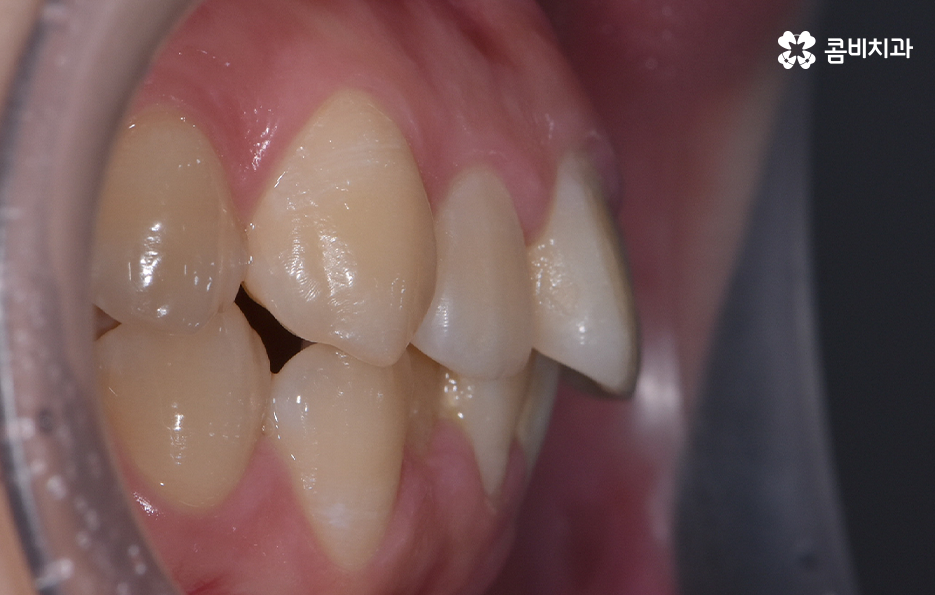

오늘 덧니 비발치 교정 사례로 보시는 환자분의 경우에는 윗니와 아랫니 앞니 부분에 조금씩 덧니가 있는 상태로 덧니를 제외하면 대체적으로 치열 상태는 고른 편이며 덧니 교정 사례 중에서는 돌출입도 함께 개선해야 하는 경우가 많지만 위 환자분의 경우에는 돌출입의 정도가 양호했고 입술라인 역시도 정상 범위에 가까웠기 때문에 발치를 필요로 하지 않았지만 치아의 이동 공간과 보다 자연스러운 입술라인 그리고 얼굴형과의 조화를 고려하여 악궁 확장과 어금니 후방 이동을 적절히 활용하여 교정 치료가 진행되었다고 볼 수 있어요

대부분의 발치 교정의 경우 작은 어금니를 발치하여 치아의 이동 공간을 확보하는 경우가 많다면 덧니 비발치 교정의 경우 발치교정 만큼은 아니더라도 치아를 이동 시킬 공간을 약간이라도 확보해야 하기 때문에 악궁 확장이나 치간삭제를 하는 경우가 있으며 어금니 후방 이동이 필요할 경우에는 사랑니 발치를 해야할 수 있어요